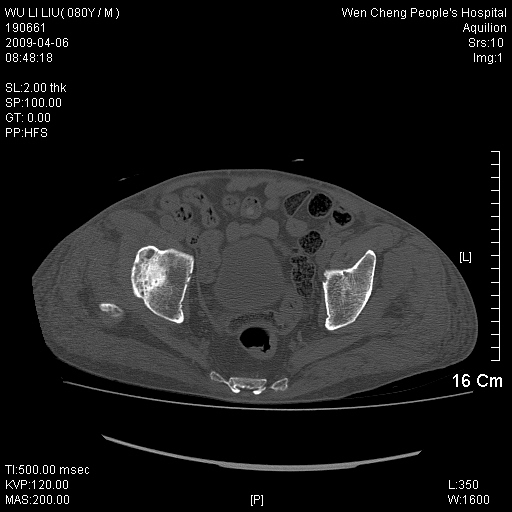

以下是引用zjzjr在2009-4-7 12:13:00的发言:[br]支持多发性转移瘤,右股骨颈骨折,腰椎亦有压缩性骨折.肝内胆管结石伴胆内外胆管扩张,左肾结石.

以下是引用liaoqiang在2009-4-7 8:44:00的发言:[br]考虑多发性骨髓瘤伴肝肺转移、肝内胆管结石、左肾结石、右股骨颈骨折。

以下是引用余辉在2009-4-7 8:52:00的发言:[br]椎骨及骨盆骨质疏松,骨破坏主要累及椎体,各骨破坏较广泛,各病灶边缘均较清晰锐利,血沉增快,白细胞增高.支持考虑多发骨髓瘤,建议查本尿周氏蛋白.[br]胆内胆管及左肾结石[br]右股骨颈骨折,考虑病理性